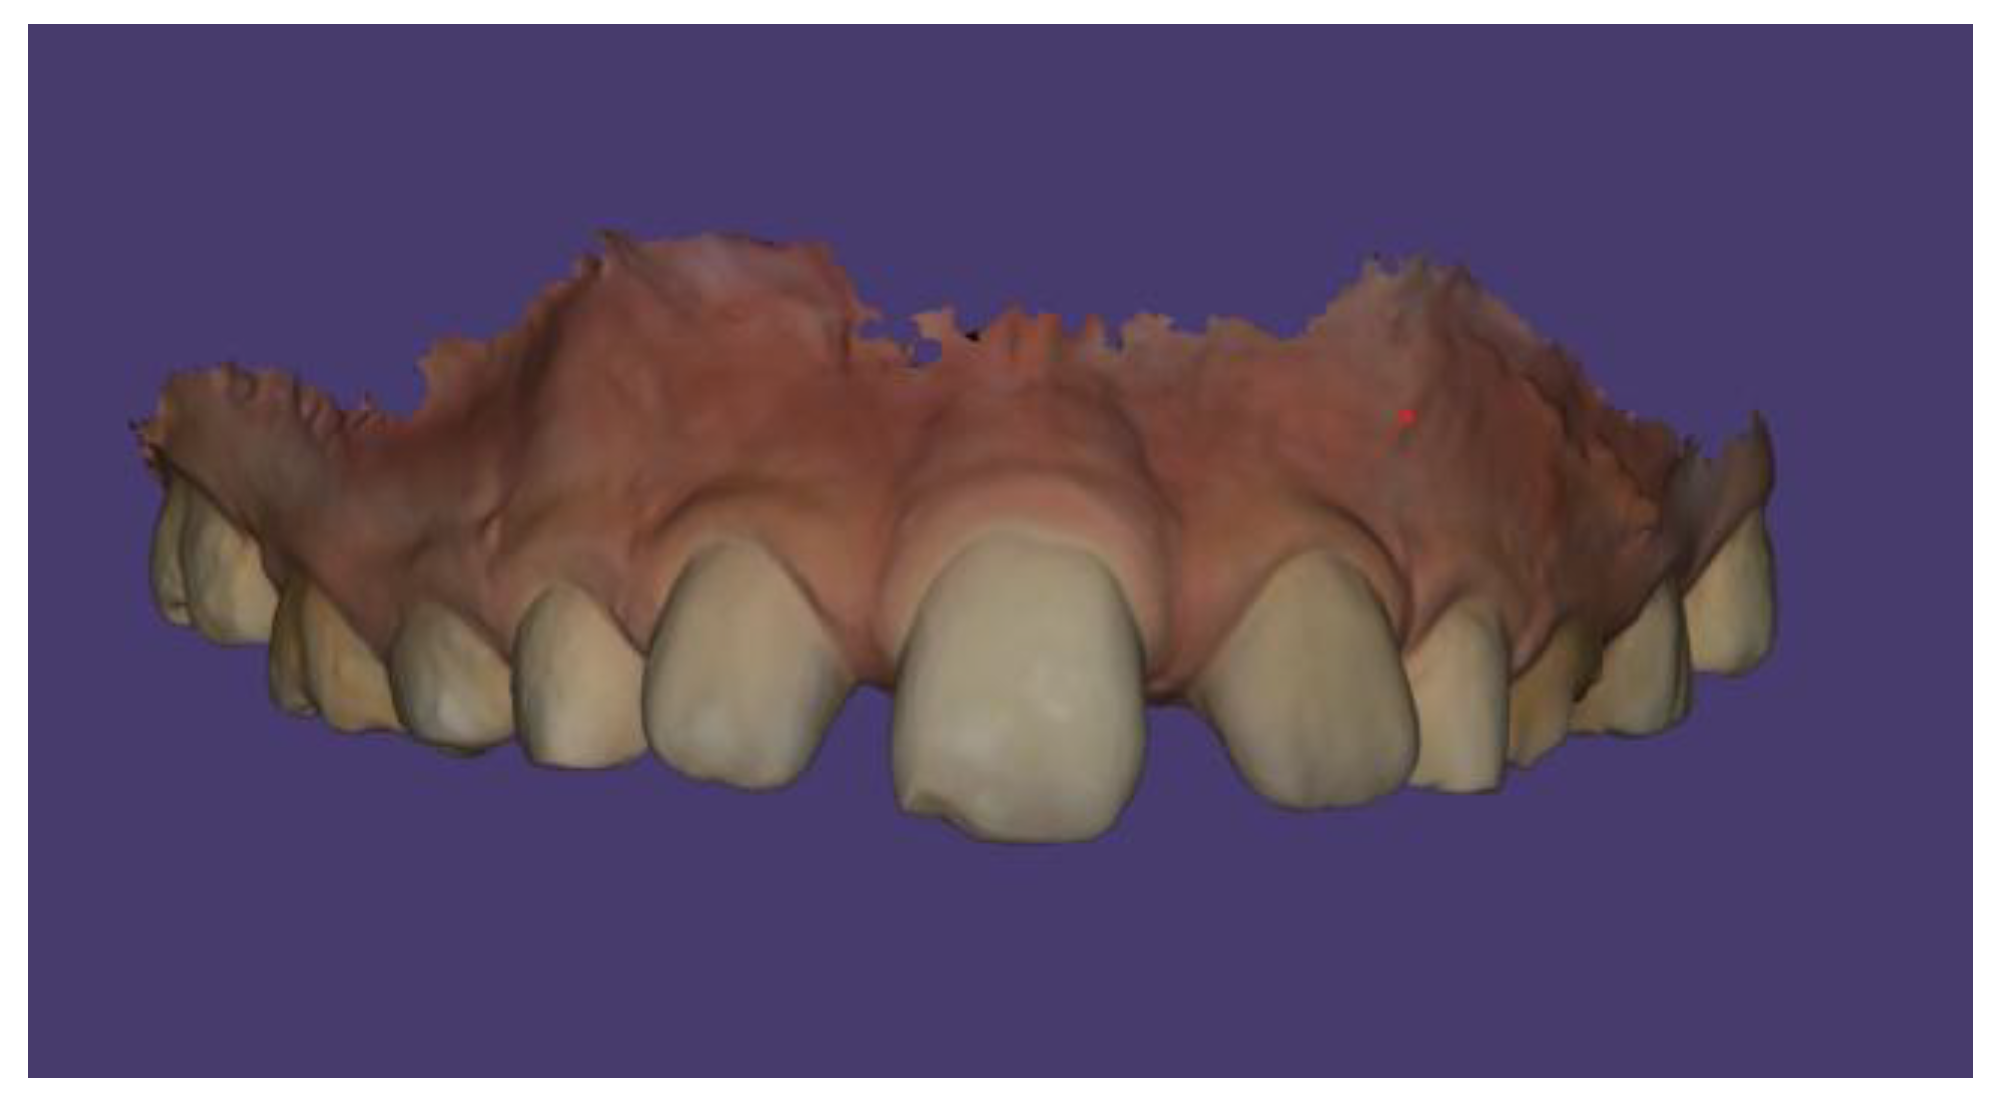

Case Description